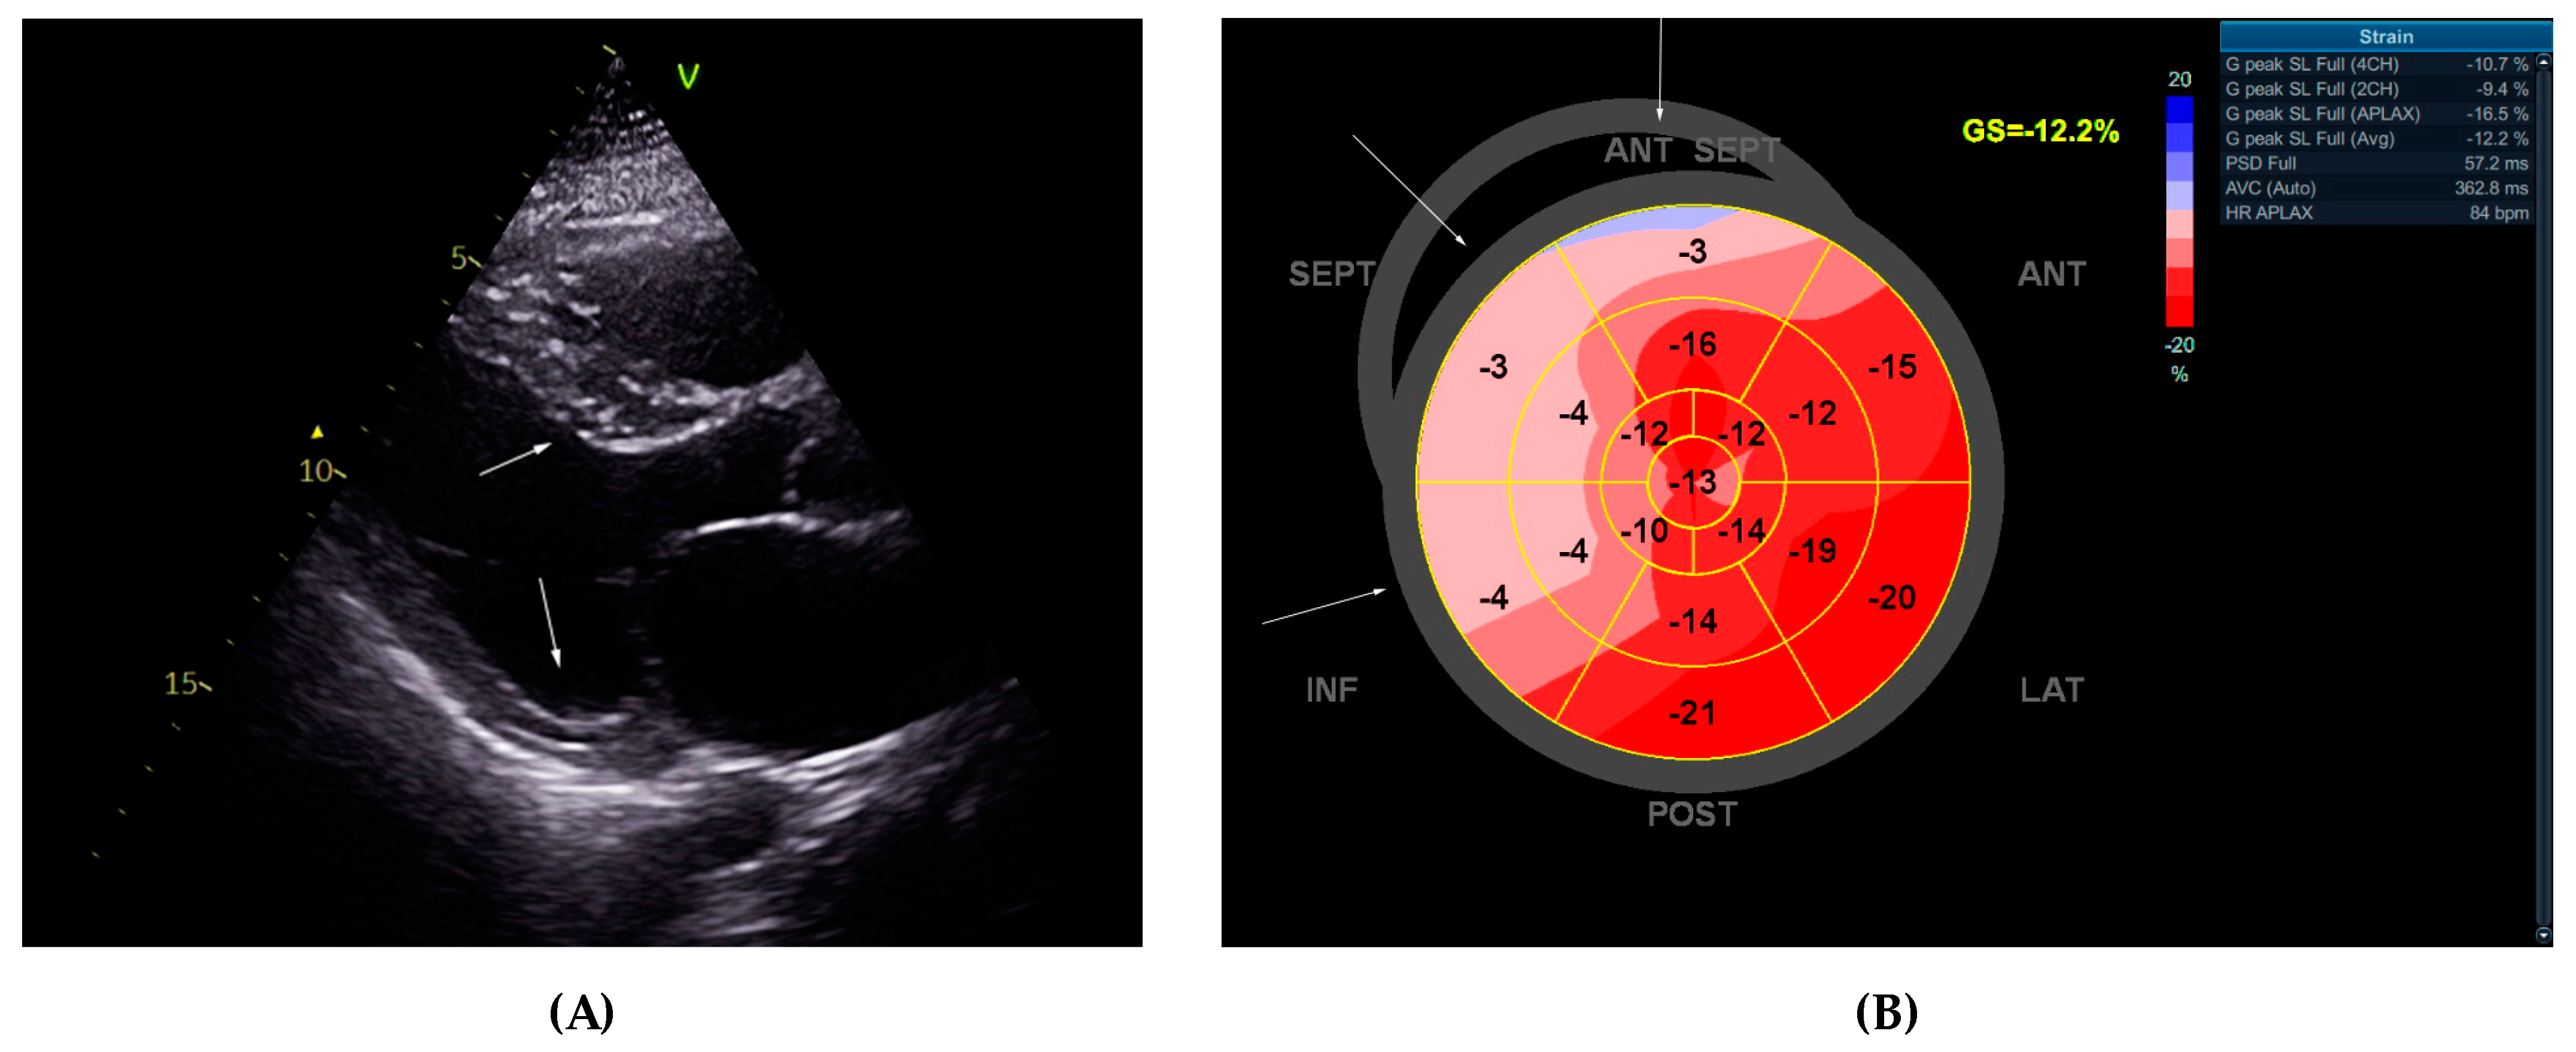

2.1. Echocardiographic Study

| LA A-P Diameter | LA Volume | Ind. LA A-P | LAVI | RA Diameters | RA Area | RA Volume | Ind. RA Volume |

|---|---|---|---|---|---|---|---|

| 56 mm | 130 mL | 22.2 mm/m2 | 52 mL/m2 | 40 × 59 mm | 24 cm2 | 65 mL | 26 mL/m2 |

| IVSd | PWLVd | IVSd/PWLVd | LV EDD | LV ESD | LV EDV | LV ESV | LVEF |

| 16–17 mm; | 8 mm; | 2 | 48 mm | 40 mm | 163 mL | 98 mL | 35–40% |

| LV GLS | PSD | MV E-wave | e’sept. | e’lat. | E/e’ ratio | TAPSE | IVC |

| 12.2% | 57.2 ms | 1.01 m/s | 0.06 m/s | 0.08 m/s | 14.42 | 16 mm | 20 mm, no collapse |

| RV basal diameter | RV EDA | RV ESA | RV FAC | RVFW | PA AT | TR Vmax | Kinetics |

| 41 mm | 21.4 cm2 | 14 cm2 | 35% | 4 mm | 148 ms | 2.2 m/s | Diffuse hypokinesia |